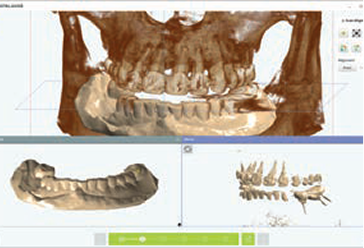

ICP (Iterative Closest Point)

Manual Control

Align 3D Model & CT

Fixture Simulation